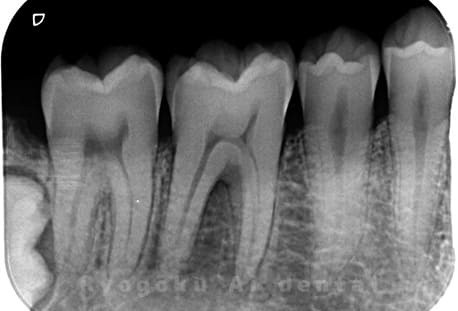

Case02

- 原因

- 慢性根尖性歯周炎

- 治療期間

- 3ヶ月

- 治療内容

- マイクロエンド

- 治療費用

- 121,000円

噛むと痛みが出る、とのことで来院した患者様です。他院での根管治療を終えてましたが、根尖病変を認めるため、マイクロエンドを行いました。

<リスク・副作用>

術後は痛み、腫れ、痺れなどの副作用が生じる場合があります。症状が再発する可能性があります。